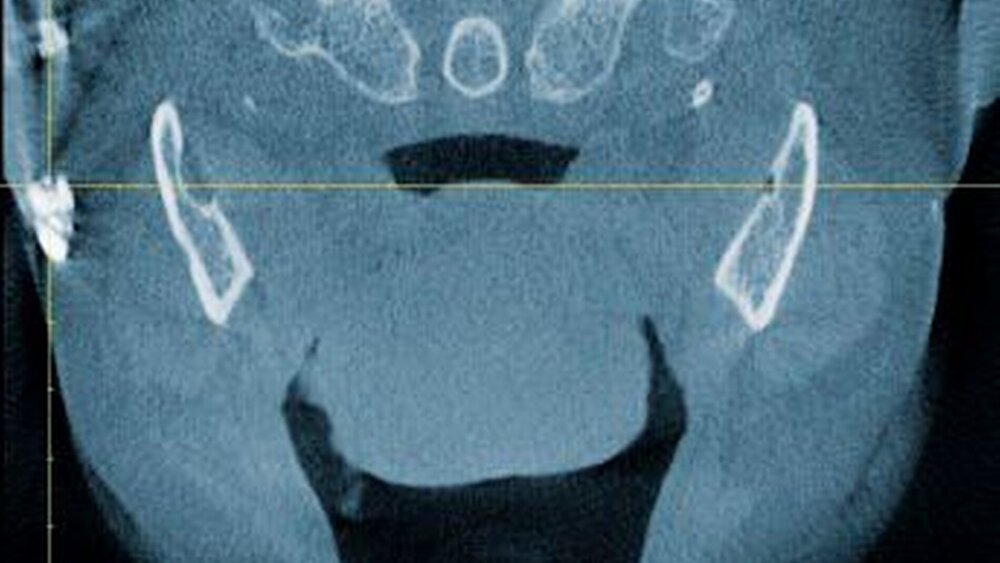

Zur genauen räumlichen Zuordnung der Verschattungen unterhalb der Incisurae semilunares wurde eine dentale digitale volumentomografische Untersuchung durchgeführt (Abbildungen 2 bis 4).